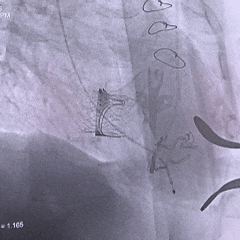

术中影像

28mm球囊后扩,瓣膜形态明显改善

最终评估可见瓣膜形态、位置均理想